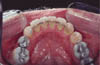

These fixed retainers are constructed from .0195” or .0175” multistrand stainless steel archwire. An indirect technique is used to adapt the wire passively to a working model. The retainer is attached to the lingual surface of the teeth using floss or a specially constructed jig and is bonded in position using a light-cured composite resin. Care should be taken to clear the occlusion during placement in the maxillary arch. Excess bond on the lingual surfaces and at the gingival margins should be carefully removed, and the area polished giving smooth even surfaces which are easy to clean (Fig. 1).

The inherent flexibility of this multistrand archwire allows for physiologic tooth movement and prevents bond fracture due to occlusal forces. Periodontal ligament stability is also readily achieved using this non-rigid system.19,20 Disadvantages of this mode of retention include possible hygiene difficulties, and localized relapse where there is a partial debond of the retainer. Undetected debonds also carry the risk of decalcification and caries.

Figure 1

Click to see the larger image

Fig 1: Bonded multistrand retainer.